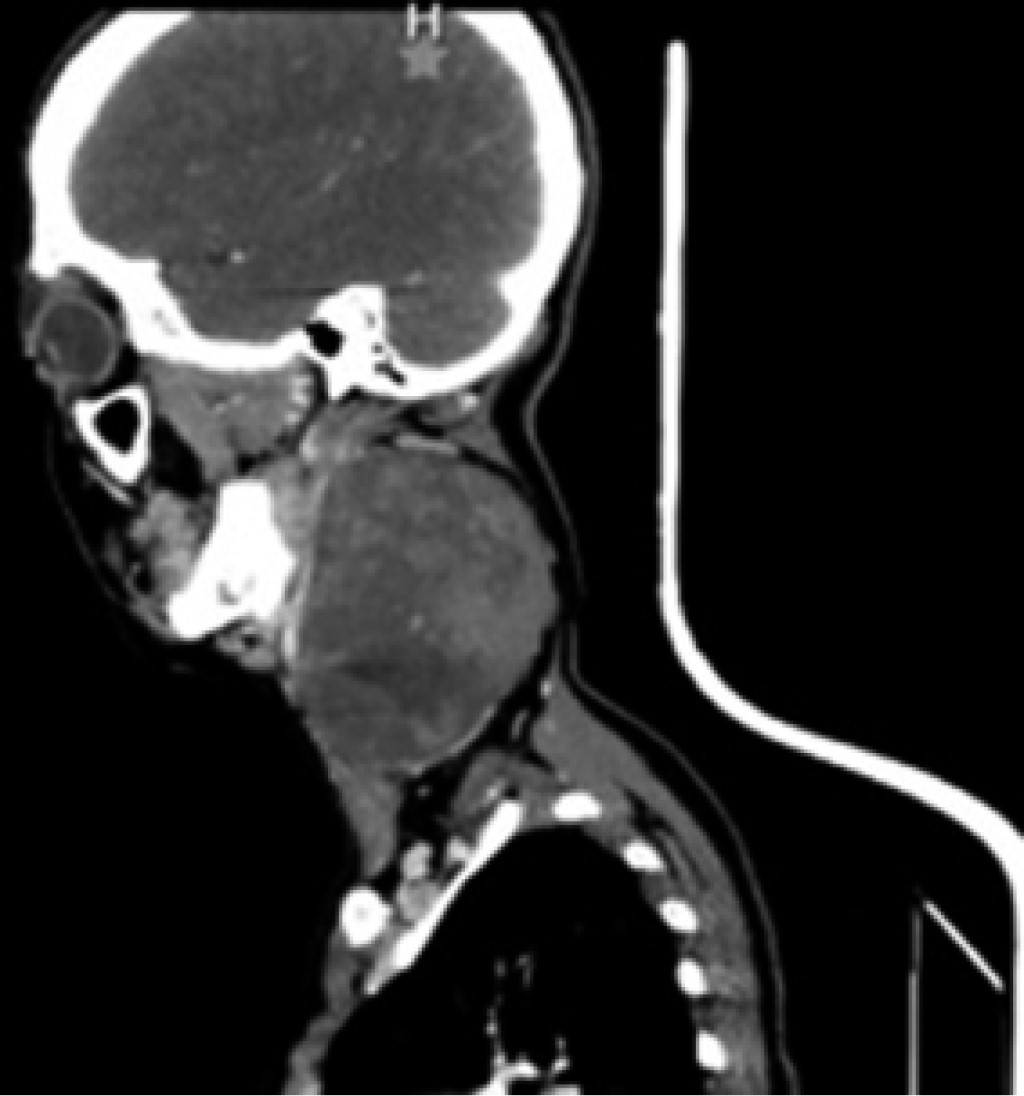

Physical examination revealed the presence of a cervical tumor measuring approximately 12 × 8 × 10 cm, indurated, and fixed to deep planes, covering regions II, III, and Va of the left hemi collar (Figure 1); it was slightly painful on palpation with a 3/10 intensity on VAS, without difficulty in opening the mouth, no facial asymmetry nor airway involvement.

There was no systemic inflammatory response syndrome, hemodynamic instability, or cardiopulmonary compromise. As a diagnostic complement, a CT scan is requested, which reports a large, rounded mass of solid appearance with regular edges, well delimited, heterogeneous, predominantly hypodense, with small areas of lower density inside, without identifying calcifications, with a density between 24 and 37 HU and that after the administration of intravenous contrast presents a density between 33 and 87 HU. It was in the left parapharyngeal level of 6.6 × 7.5 × 9.2 cm, as a left parapharyngeal space lesion with a suspected branchial cyst versus pleomorphic adenoma versus hemorrhagic branchial cyst (Figures 2, 3 and 4).